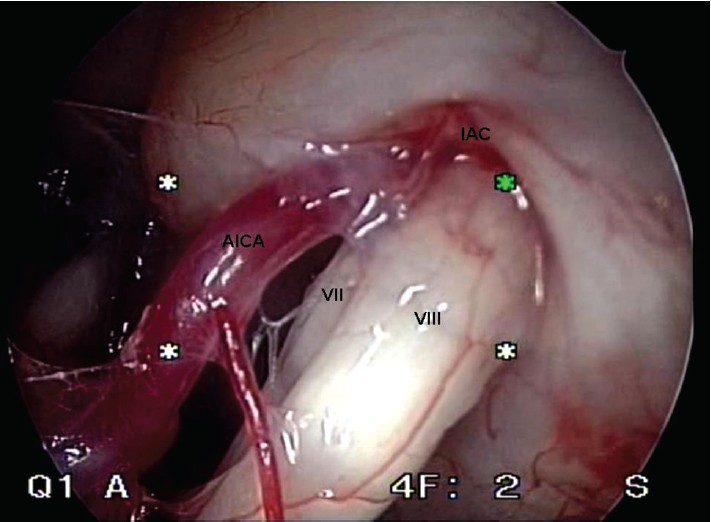

Vestibül-koklear sinir için, bir nörovasküler temasın tek varlığı tek başına yeterli değildir; bir veya daha fazla ortak kriterin varlığı olması, teşhisi için gereklidir. Bir başka önemli bulgu, vestibülokoklear sinirde bir baskı izinin varlığı ve siniri çevreleyen vasküler damarın loop'u ile sinir çapının azalmasıdır. Son olarak interakustik kanalda bir arteriyel döngü varlığı olabilir. Kulak çınlamasına veya vertigoya neden olabilir. ( [Şekil 3] )

Bu sinir, iç kulağın denge kısmı ve işitme ile ilgili alanlarının siniridir. Bir kemik kanalda içinden geçer bu inter akustik kanal adı verilen yapı içinde aynı anda damarlar, yüz siniri (7. sinir) ve vestibulokoklear sinir (8. sinir – işitme denge siniri) bulunur. Vestibüler paroksisminin sekizinci kraniyal sinirin (vestibüloklear -işitme denge siniri ) bir mikro arter tarafından sıkışması nedeniyle oluştuğu varsayılmaktadır.

Cerrahi: Tıbbi tedavi istenen sonuca ulaşılamamış ise ameliyat yapılabilir. Vestibüler siniri sıkıştıran bir vasküler lup (katlanma – sıkışma yapan kısım) mikrovasküler dekompresyon adı verilen işlem ile sinire yansıyan baskı ortadan kaldırılabilir. Uzman ellerde minimal morbidite ile endoskopik olarak yapılabilir.